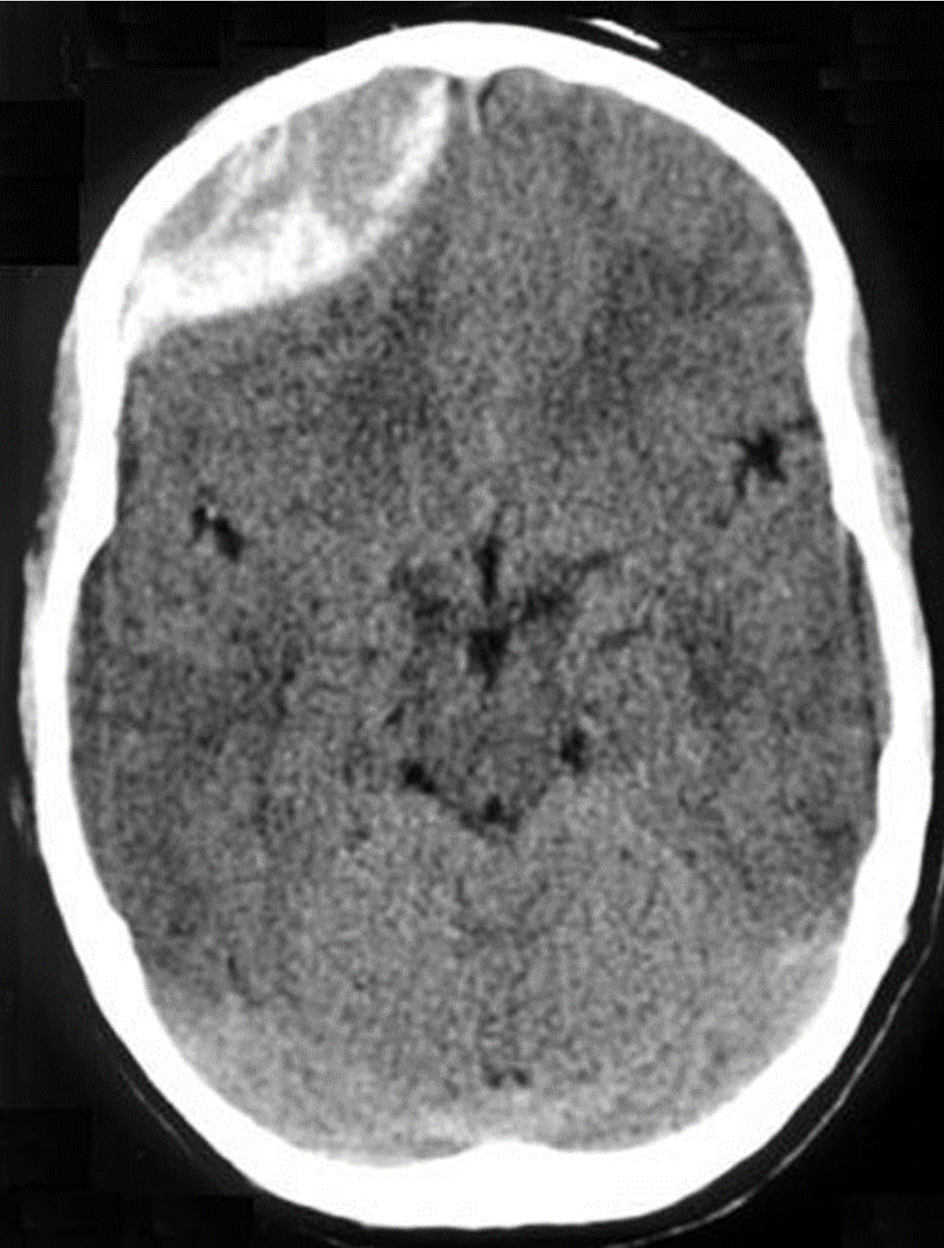

- Epidural Hematomas: Occur when there is bleeding into the space between the skull and the dura mater. CT scan will show a convex, lens-shaped collection of blood. Blood generally does not cross suture lines. Many of these hemorrhages are caused by laceration of the middle meningeal artery, although venous bleeds can also occur. The classic presentation is a brief loss of consciousness with the trauma, followed by a lucid period and then deterioration. As epidural hematomas can accumulate rapidly, patients may change quickly and a timely diagnosis and neurosurgical intervention are key.

Figure: Epidural hematoma. Image courtesy of Jpogi. Image used under the Creative Commons Attribution-Share Alike 3.0 Unported License.

- Subdural Hematomas: Occur when there is bleeding into the space between the dura and arachnoid membranes. They appear as concave or crescent-shaped collections of blood on CT scan and can cross suture lines. These are generally caused by tears to the bridging veins between the cortex and venous sinuses. The hemorrhage occurs more slowly than in epidural hematomas, although still over a period of a few hours.

Figure: Subdural hematoma. Image courtesy of Dr. James Heilman. Image used under the Creative Commons Attribution-Share Alike 3.0 Unported license.

- Subarachnoid Hematomas: Occur when there is bleeding into the space between the arachnoid membrane and the pia mater that surrounds the brain.

Figure: Subarachnoid Hemorrhage. Image courtesy of Dr. James Heilman. Image used under the Creative Commons Attribution-Share Alike 3.0 Unported license.

When evaluating a CT scan with an intracranial hemorrhage, it is important to not only identify the type of hemorrhage, but also to note the size and whether the lesion is causing mass effect or midline shift.